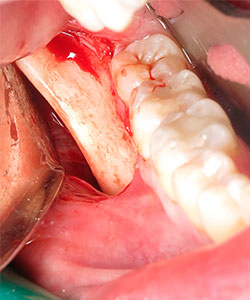

La cirugía se realiza con anestesia local (articaína 4% con 1:100000 de epinefrina). Se realiza una anestesia local del nervio dentario de la zona donadora y una infiltración subperióstica en la zona receptora. La incisión con hoja del no 15 se hace preservando las papilas. Se levanta un colgajo mucoperióstico en la zona receptora preservando las papilas de los dientes adyacentes. Se mide el tamaño de la zona a injertar y se realiza una incisión recta desde el inicio de la rama ascendente mandibular hasta el segundo molar mandibular. Se diseca lateralmente la mucosa hasta lograr exponer la parte posterior del cuerpo de la mandíbula.

Se irriga profusamente la zona dadora con suero fisiológico y suturamos la incisión con catgut crómico. Una vez obtenido el injerto se preserva envuelto en una gasa húmeda con suero fisiológico isotónico y se remodela con la ayuda de unas pinzas gubia hasta adaptarse a la forma del defecto a injertar. La zona dadora puede prepararse mediante la perforación de la cortical externa con el fin de obtener un sangrado que facilite la revascularización del injerto.